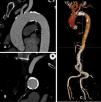

Prior to the procedure, an echocardiography showing a peak velocity in aortic valve of 5 m/s, with mean pressure gradient of 69 mmHg and an area of valve of 0.95 cm2 and a computerized tomography (CT) scan demonstrating a tricuspid aortic valve of 24.9 mm diameter according to 78.2 mm perimeter of aortic annulus had been performed. The valvular calcium score was 3645, with a valvular area of 0.8 cm2. A severe calcification of the aortic arch was also noted on the CT scan (Figure 1A–C).

A SAPIEN 3 ULTRA valve was implanted (Supplemental video 1). Pre-dilation was performed with a valve balloon dilated to 22 mm. After the implantation of the valve, a moderate residual leak was noted (Supplemental videos 2 and 3). Post-dilation with the same balloon was attempted, encountering difficulty with balloon progression (Supplemental video 4). At this time, the patient presented with hemodynamic collapse and cardiac arrest. Echocardiogram showed no pericardial effusion, excluding annular rupture, and the coronary arteries were patent. While performing advanced life support maneuvers, an aortography was performed, revealing a rupture at the transition between the aortic arch and the descending aorta (Figure 2 and Supplemental video 5). Tamponade with a 28 mm balloon was performed and a TEVAR 28 mm was implanted with subsequent dilation using a RELIANT balloon. While resolution of the active rupture was achieved angiographically (Figure 3 and Supplemental videos 6–8), and despite 55 minutes of resuscitation maneuvers, cardiac rhythm could not be restored.